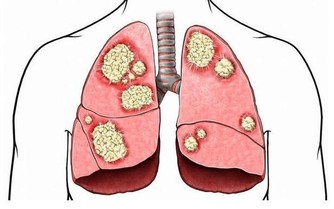

腎臟好比人體的污水淨化站,擔負著過濾、消除有害物質的功能,同時保護對生命活動有重要作用的蛋白質、水分和鹽類不致流失,保持人體水液平衡。

因此,腎臟一旦發生故障,就不能消除各種有害物質和多餘水分,還會導致大量營養物質流失,引起水液代謝失調、酸鹼平衡失調等現象,嚴重時甚至危及生命。